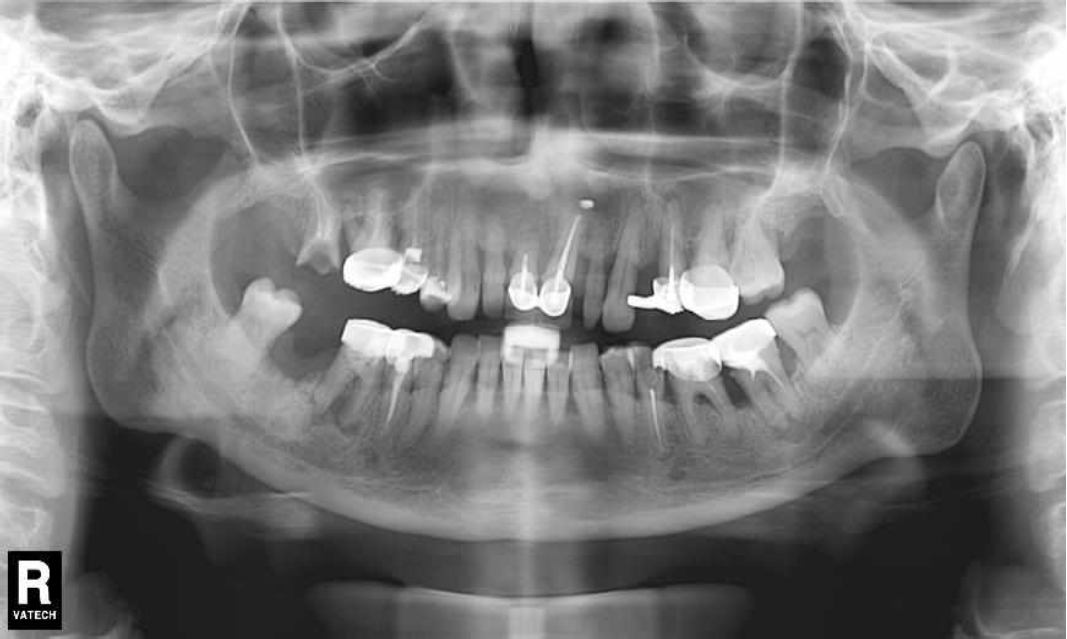

Ранее у пародонтолога не наблюдалась. При осмотре выявлены: неудовлетворительная индивидуальная гигиена полости рта, пародонтальные карманы до 7 мм, обильная кровоточивость и гноетечение из пародонтальных карманов, подвижность зубов 4.2, 4.1, 3.1, 3.2 II степени, обильные над- и поддесневые зубные отложения (рис. 1). На ортопантомограме отмечается резорбция костной ткани до ½ длины корня, очаги остеопороза (рис. 2). Пациенту был поставлен диагноз хронический генерализованный пародонтит тяжелой степени тяжести. При осмотре была составлена пародонтограмма с использованием компьютерного зондирования (рис. 3).

Рис. 2. Ортопантомограмма исходной ситуации пациента  состояния полости рта